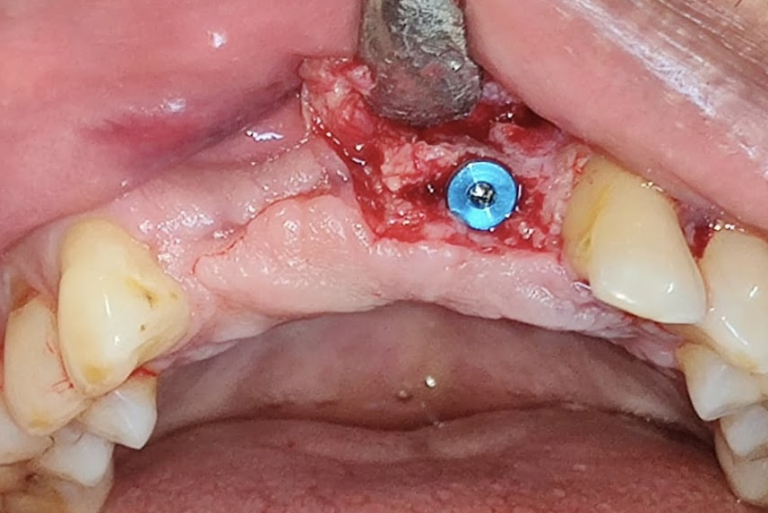

- Ridge Split surgeries for dental implants

- Guided Bone Regenerative procedures using membrane and bone grafts

- Conventional Implant Surgeries